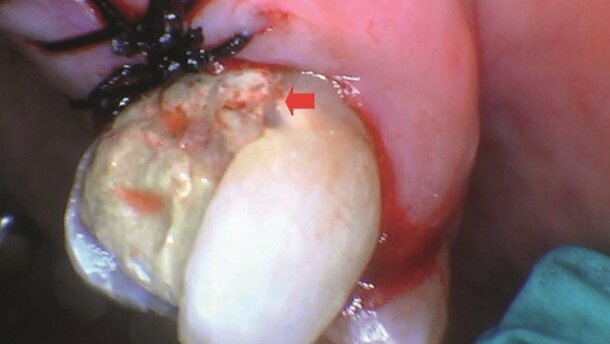

Następnie odwarstwiono płat dziąsłowy, używając tradycyjnych narzędzi periodontologicznych.¬ W celu wykonania ablacji tkanek wyrostka zębodołowego, laser Solea użyto na ustawieniach dla zębiny (Dentine Setting): wielkość plamki 1,00 mm, czas trwania impulsu 75 µs, 100% wykorzystania wody oraz 50%-100% zmiennej prędkości ze sterownika nożnego. Ustawienia te pozwoliły na ablację tkanek wyrostka, dzięki czemu osiągnięto jego biologiczną szerokość, odsłaniając jednocześnie część koronową w celu umożliwienia prawidłowej odbudowy. Wielkość plamki ustawiono na 0,25 mm dla osiągnięcia większej precyzji pracy na kości przylegającej do tkanek zęba. Należy zwrócić uwagę na dobrą perfuzję wyrostka zębodołowego. Czerwona strzałka na zdjęciu wykonanym po ablacji kości oraz szyciu (Ryc. 10) wskazuje poziom kości wyrostka w stosunku do punktu odniesienia nieopodal połączenia cementowo-szkliwnego.

Płat dziąsłowy przedstawiony jest jeszcze w stanie sprzed ich zbliżenia i zszycia (Ryc. 11). Poziom kości wyrostka zębodołowego został potwierdzony radiologicznie przed zaszyciem i porównany z poziomem oznaczonym czerwonymi strzałkami (Ryc. 12a). Płaty dziąsłowe zostały do siebie zbliżone oraz zszyte 4 jedwabnymi szwami węzełkowymi 3,0. Już po założeniu szwów można było zauważyć lepsze ułożenie tkanek dziąsła przy powierzchni dystalno-policzkowej zęba 14, jak wskazuje strzałka w punkcie odniesienia (Ryc. 12b).